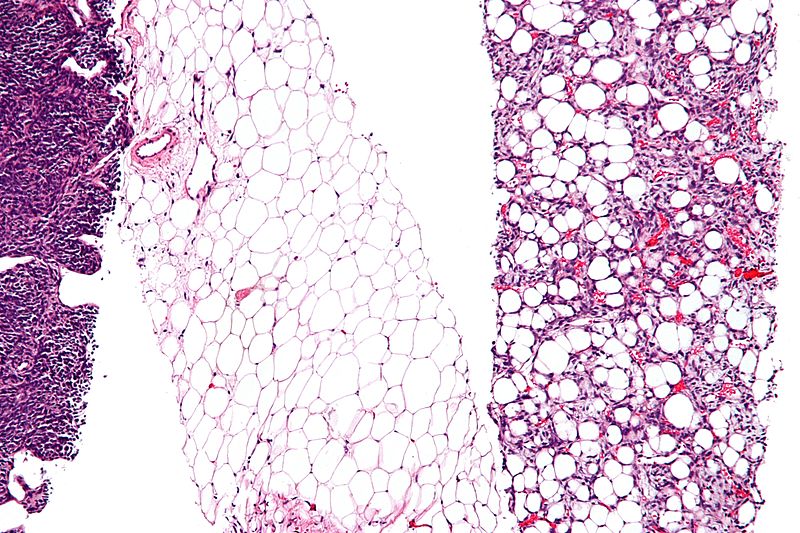

Lipoma

A lipoma is a benign tumor composed of adipose tissue that typically develops just beneath the skin.

Definitive diagnosis of lipoma is made by pathology showing a well circumscribed mass composed of benign adipocytes.